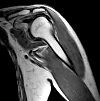

MRI of the shoulder joint.

Магнитно-резонансная томография плечевого сустава. Это томографический метод, позволяющий исследовать структуры, образующие плечевой сустав, с использованием явления ядерного магнитного резонанса. Он показывает общую конфигурацию сустава, головки плечевой кости, акромиально-ключичного сустава, синовиальных мешков, сухожильно-связочного аппарата и регионарных мышц. МРТ может обнаружить переломы, растяжения связок, аутоиммунные и воспалительные изменения, опухолевые образования, повреждения мышц и связок и растяжений связок, травмы сухожилий, синовиальный выпот и накопление геморрагической жидкости в полости суставной капсулы. При необходимости исследование дополняется внутривенным или внутрисуставным введением контрастного вещества.